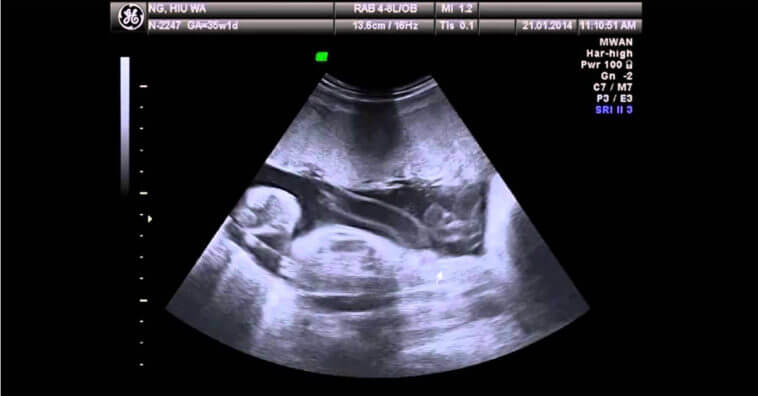

Entretanto, tudo mudou. Tinha algum tempo que Carol achava que havia algo que não estava bem. Sentia-se muito inchada, mas como fazia muito Calor em Minas Gerais, os médicos acharam que era normal. No dia 1 de abril de 2013, às 34 semanas de gestação, uma ultrassonografia confirmou o pior. O menino tinha morrido.